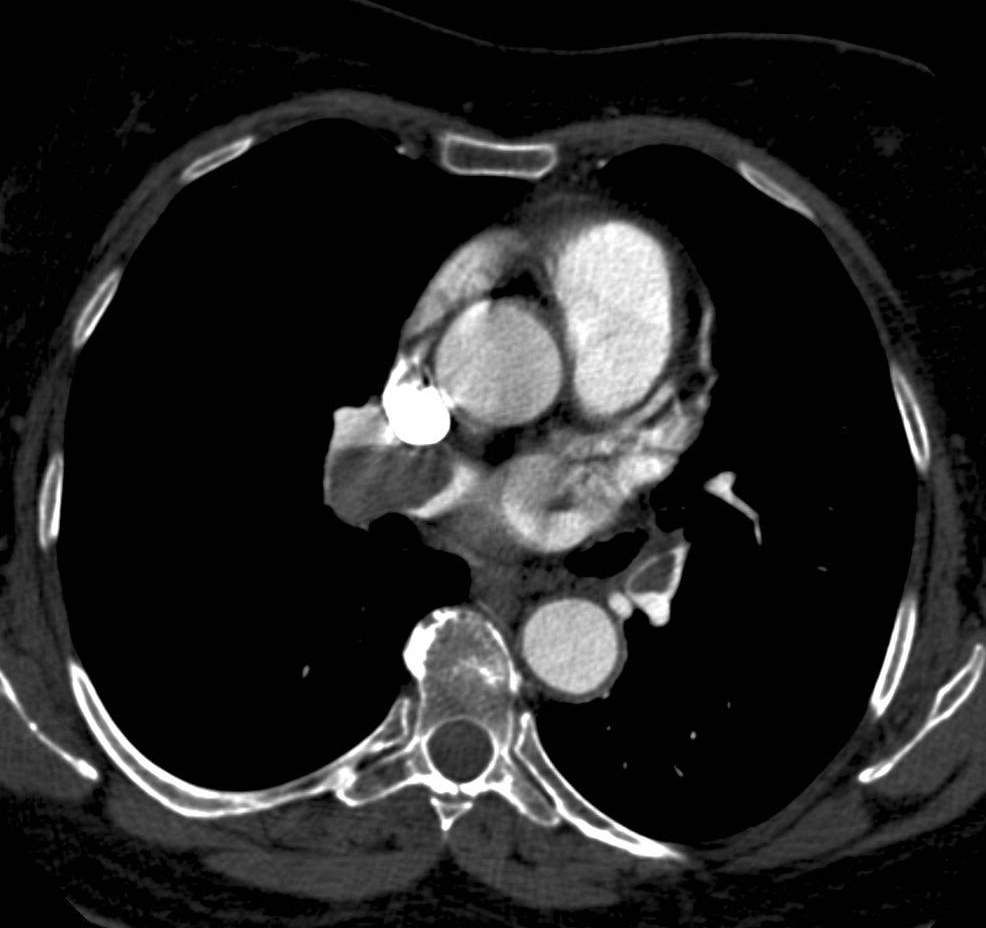

There are two main types of aorta dissection according to the Stanford classification: type “A” when the ascending aorta is involved, and type “B” when the dissection occurs distal to the origin of the left subclavian artery and it does not propagate to the level of ascending aorta or the aortic arch. The two types are distinguished because of their acute complications: type “A” dissection can cause the obstruction of the coronary trunks or, in case of a pericardial rupture, it can cause consequent pericardial tamponade and sudden death. Hence these cases require immediate surgical intervention with a cardiac surgical background. In contrary type “B” dissection can cause the acute obstruction of the abdominal aortic branches and can lead to life threatening conditions only in a subacute manner (intestinal ischemia, renal insufficiency). These conditions can also require surgical intervention (vascular surgery) but they rarely need immediate surgery. Both dissection types have the late stage complication of the development of aneurysm that occurs due to the weakened and constantly expanding vessel wall, which constitutes a growing risk for aortic rupture.

Primary diagnostic imaging is usually performed as an emergency examination, patients are often unstable, or gravely ill and in poor condition. Therefore, CTA is a most advantageous method; it can provide a diagnostic quality imaging even on a non-cooperative patient with. It is crucial to determine the type of dissection (A or B-), the involvement of the supraaortic and abdominal branches, the origin of the side branches, and the anatomy of the false and the real lumen and their permeability. A highly pulsating aortic root can cause diagnostic problems because of the vessel movement. The artifact caused by the moving arterial wall can mimic an intimal-flap, especially at the root of the ascending aorta. However, this can be avoided with ECG gated examination; hence patients with symptoms of acute coronary syndrome should be directed to a centum where ECG gated imaging is available.

Image

The lumen is divided by the detached intimal layer that can be followed from the origin of the left subclavian artery to the descending aorta.

The real lumen shows a fast filling and a more intense contrast enhancement,

while the false lumen shows a less intense contrast enhancement due to its decreased flow.

Fig. 26., 27., 28.: Type B aortic dissection CT angiography

On axial slices, an intima flap can be seen in the ascending aorta

The dissection spreads also into the lumen of supraaortic arteries

Fig. 29., 30.: Type A aortic dissection, ECG-gated CTA examination